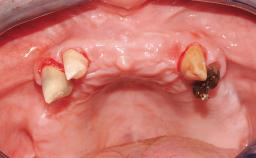

Immediate Loading of Four Implants in the Mandible and Final Restoration with a Full-Arch Metal Framework FDP

Pedro Tortamano, Luiz Otávio Alves Camargo

A fully edentulous 65-year-old woman was referred to our clinic for esthetic and functional dental rehabilitation. The patient presented with inadequate complete maxillary and mandibular prostheses, insufficient vertical dimension, and extensive tooth wear. The clinical examination and anamnesis showed no local or systemic contraindications, no signs or symptoms of bruxism, and an absence of smoking habits. The treatment proposed was implant placement in the mandibular interforaminal area and immediate loading with a fixed definitive prosthesis. A removable mucosa-supported complete prosthesis was indicated for the upper jaw, since its bone structure offered satisfactory retention and the financial condition of the patient disfavored a full-mouth implant-supported rehabilitation.

# of Implants 4

Type of Implants One-Piece

Attachment One-Piece

Prosthesis Type FDP